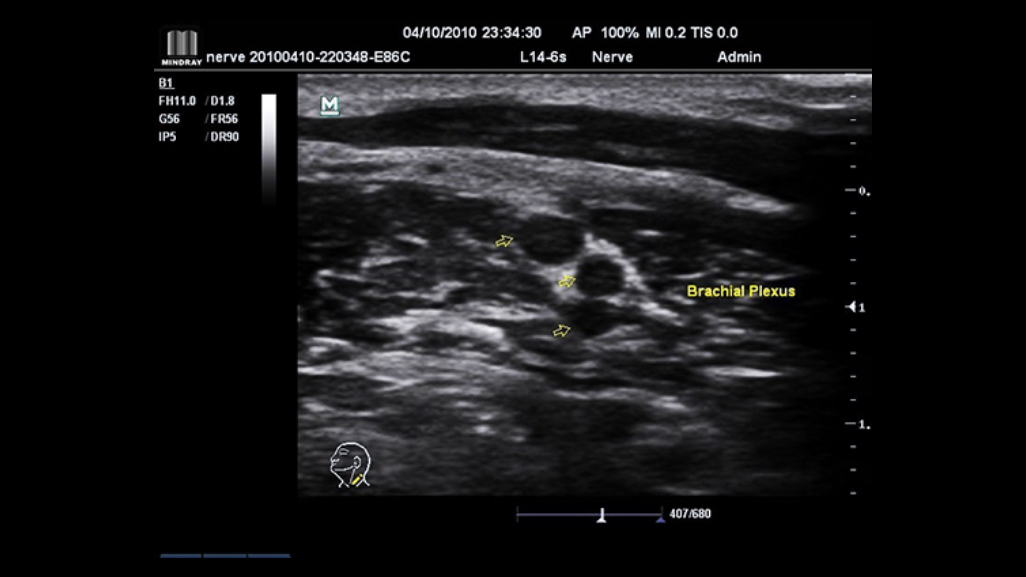

iNeedle

The totally new iNeedle is able to recognize and adapt the puncture angle automatically, enhancing both needle tip and pathway clearly.